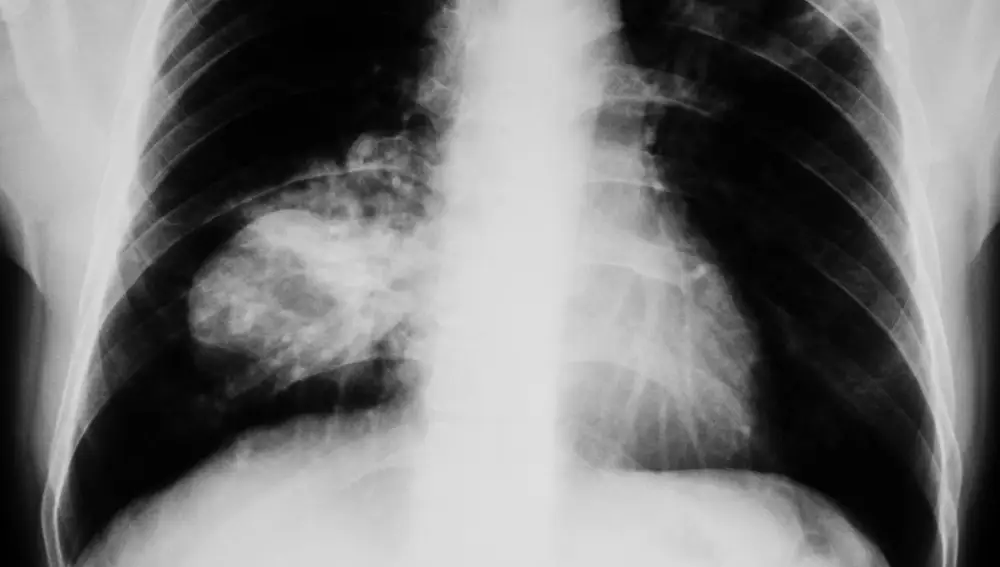

- El 56% de los pacientes se diagnostica en estadio avanzado (III o IV).

- Solo un 10% se detecta en fases tempranas.

- Cuando se diagnostica en estadio I, la supervivencia supera el 80%.

- En estadio IV, solo el 5% supera los cinco años

Esta disparidad evidencia que el diagnóstico precoz es clave, pero también que la enfermedad suele avanzar sin síntomas claros.